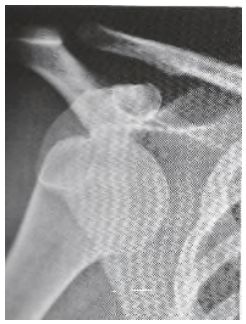

58 肩關節正面 X 光片(如圖),下列何者正確? (A)肩鎖關節脫位 (B)喙突下脫位 (C)盂下脫位 (D)鎖骨下脫位